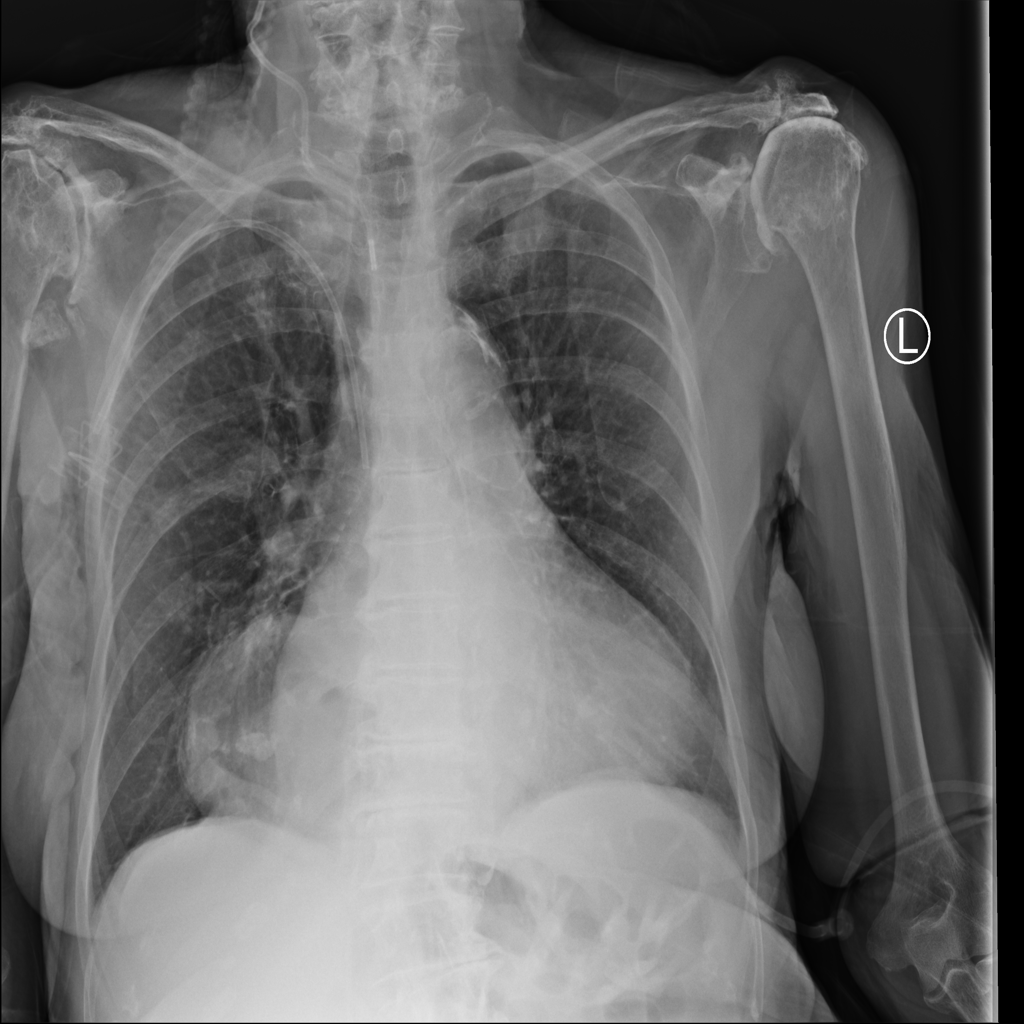

PAT-C048 · IMG-001Hernia

PAT-C048 · IMG-001

PA